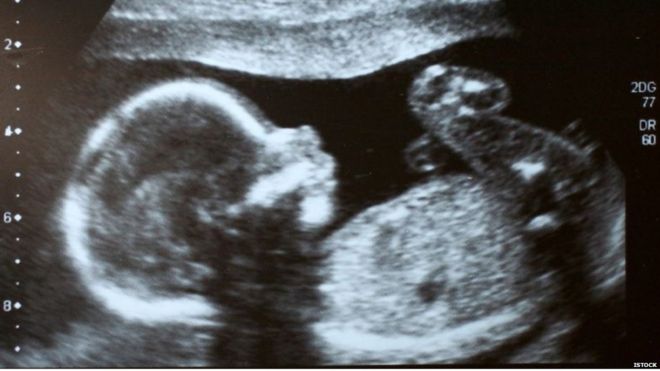

उनका पेट पूरी तरह से फ़्लैट था जबकि प्रेगनेंसी के तीसरे महीने से ही बेबी बंप नज़र आने लगता है.

और जो दर्द उन्हें हो रहा है वो लेबर पेन है. दो घंटे बाद उनकी गोद में मॉली थी, अब वो दो साल की एक स्वस्थ बच्ची है.